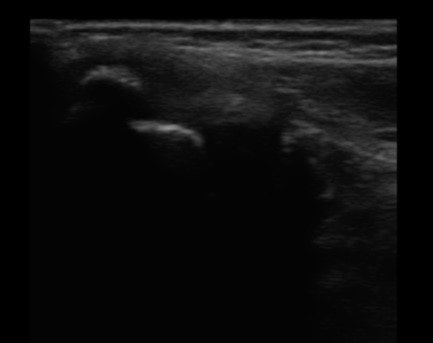

①画像診断を使ったしっかりとした状態把握

まず超音波エコーで画像診断を行い、炎症の程度、腫れの状態、剥離骨折を起こしていないかなどのチェックを画像診断でしっかりと行い、練習を休まなければいけないのか、などの判断や改善までの治療計画を考えていきます。